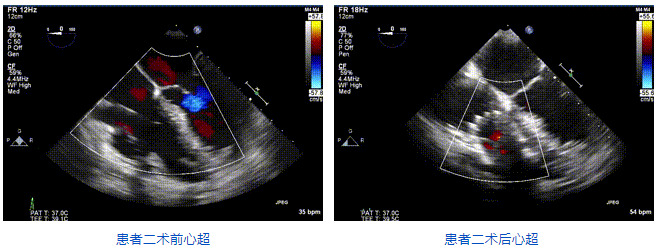

本周三例接受LuX-Valve Plus經血管三尖瓣置換術的患者中,第一例患者為冠狀動脈旁路移植術+Bentall+二尖瓣成形術后;第二例患者為永久起搏器植入術后,存在跨三尖瓣導線;第三例患者合并房顫、房缺及左心耳封堵術后。

三例患者入院后,葛均波院士團隊周達新教授、潘文志教授、張源博士、陳莎莎博士及心超室的潘翠珍教授、李偉教授對患者的情況進行詳細評估和討論,最終決定為三例患者選擇LuX-Valve Plus40mm、50mm和50mm型號的瓣膜進行手術治療。手術后即刻拔除氣管插管,術后患者三尖瓣反流癥狀得到顯著改善,復查心超結果顯示人工三尖瓣瓣膜支架固定穩定,瓣葉關閉形態未見異常,未見明顯反流。